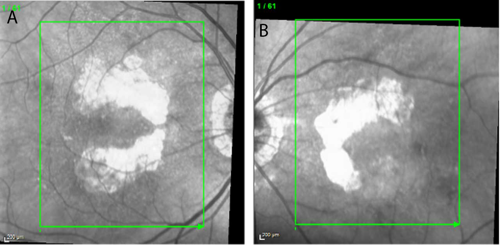

At a recent visit to his optometrist, the patient had been diagnosed with advanced dry AMD with bilateral nonsubfoveal GA. Baseline near-infrared imaging revealed multifocal lesions of 9.11 mm² OD and 5.37 mm² OS. Best-corrected visual acuity (VA) was 20/20 OD and 20/30 OS. Notably, there was no evidence of choroidal neovascularization.

Over the first year of treatment, VA remained stable. VA in the patient’s right eye fluctuated between 20/20 and 20/25, while that in the left eye ranged between 20/25 and 20/30. Imaging suggested continued enlargement of GA lesions, although the growth rate appeared slower compared with the rapid progression documented in the months prior to the start of treatment (Figures 1 and 2). Equally important, the patient was able to maintain his independence, continued to drive, and remained the caregiver for his wife—outcomes that reflected his own treatment goals.

In this patient, bilateral nonsubfoveal lesions provided a strong rationale for early intervention. Pretreatment imaging showed significant lesion growth during the 5 months between May and October 2023. After treatment, the lesions continued to grow but the growth rate was likely slowed owing to the intervention.